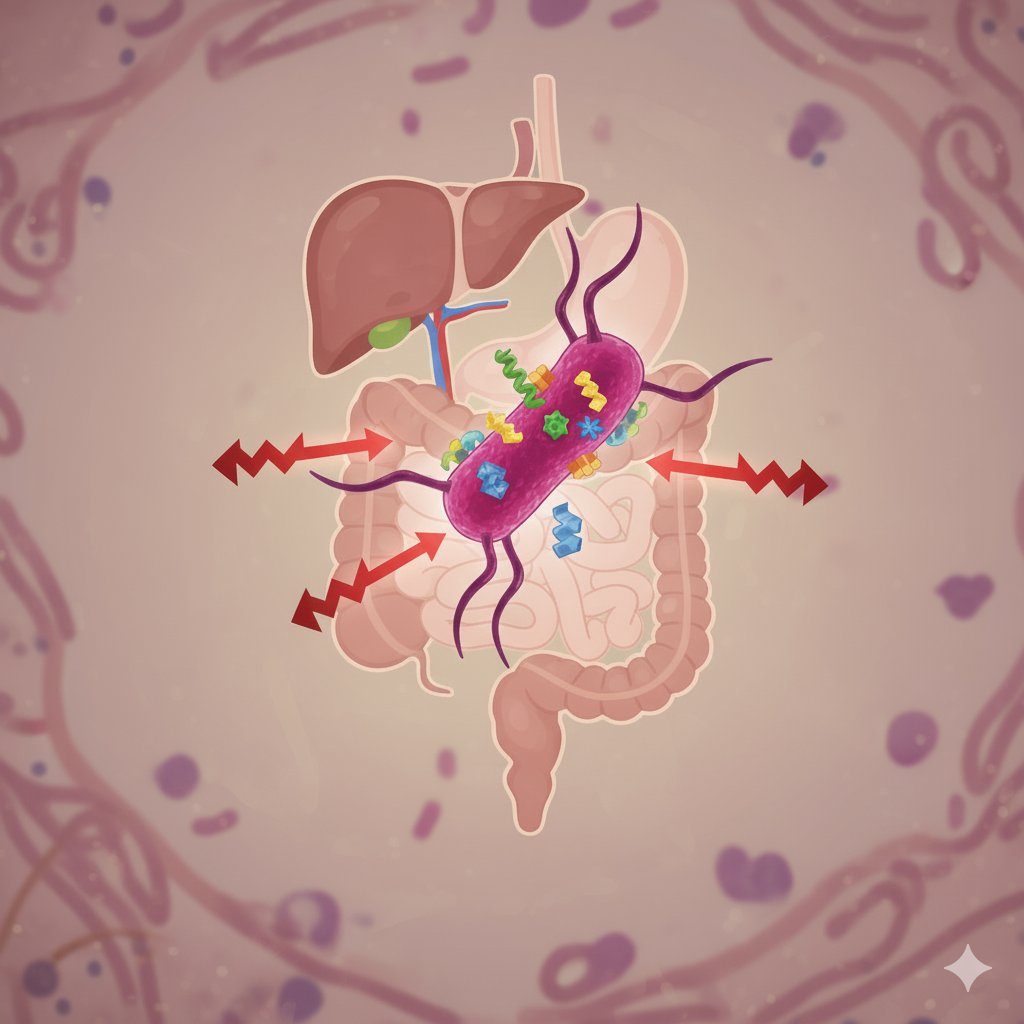

La asociación entre Helicobacter pylori y el espectro de cánceres digestivos. Esta revisión analiza el papel emergente de Helicobacter pylori más allá del estómago, destacando su asociación con distintos tipos de cánceres digestivos como el hepático, biliar, esofágico, colorrectal y pancreático. Aunque es un carcinógeno gástrico bien establecido, cada vez hay más evidencia que lo vincula con neoplasias extragástricas a través de mecanismos como la inflamación crónica y la acción de factores de virulencia. La solidez de estas asociaciones varía según el tipo de cáncer, siendo más consistente en los casos de cáncer hepático y biliar. Les invitamos a leer el artículo «Beyond the stomach: the association between Helicobacter pylori and the spectrum of digestive cancers», que explora el vínculo emergente entre H. pylori y diversos cánceres digestivos extragástricos. Un recurso esencial para actualizar su conocimiento sobre el impacto de esta bacteria en el cáncer hepático, biliar, esofágico, colorrectal y pancreático. 👉 ¡Acceda al artículo completo y profundice en los mecanismos subyacentes y las implicaciones terapéuticas! https://pubmed.ncbi.nlm.nih.gov/40964055/